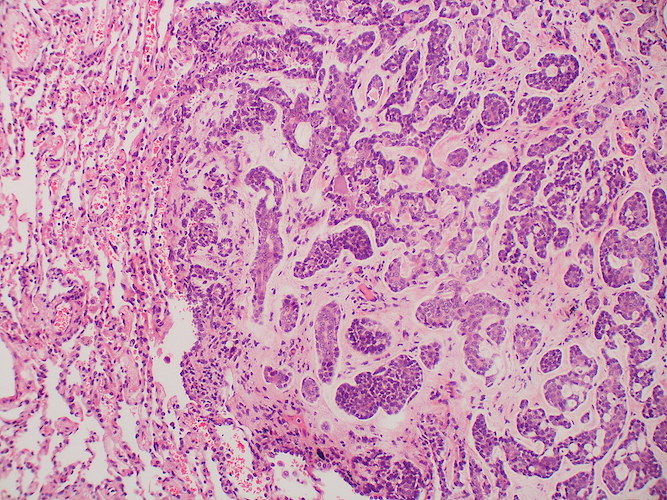

Tässä kirjoituksen ensimmäisessä osassa tarkastelemme kasvaimen mikroskooppista kasvutapaa ja rakennetta, jotka yleensä käsitellään lausunnon kuvailuosan kahdessa ensimmäisessä lauseessa. Nämä piirteet patologi arvioi ennen yksittäisten kasvainsolujen arviointia, mistä lisää kirjoituksen toisessa osassa.

- Rakenne Epiteliaaliset kasvaimet muodostovat tyypillisesti tubuluksia, rauhasia ja solusaarekkeita, kun taas sukkulasoluiset kasvaimet muodostavat solujuosteita ja -pyörteitä. Pyörösoluisille kasvaimille on tyypillistä tasaisten solulaattojen ja -mattojen muodostaminen. Solukko voi myös olla löyhää tai tiivistä. Kasvaimen pahanlaatuisuuden kasvaessa usein myös kasvutapa muuttuu huonommin erilaistuneeksi eikä kasvainsolukko muodosta enää selviä, tunnistettavia rakenteita.

- Strooma Kasvaimen tukikudos eli strooma arvioidaan aina kasvaimia diagnosoitaessa. Tyypillisesti stroma koostuu sidekudoksesta ja verisuonista (ns. fibrovaskulaarinen strooma). Epiteliaalisilla kasvaimilla strooma on yleensä runsas ja mesenkymaalisilla kasvaimilla niukka. Pahanlaatuiset epiteliaaliset kasvaimet voivat stimuloida ympärilleen voimakasta strooman muodostusta, mitä kutsutaan desmoplasiaksi. Stroomaa ei kuitenkaan pidä sekoittaa mahdolliseen solujen väliaineeseen, jonka tuottaminen on monille mesenkymaalisille kasvaimille ominaista. Esimerkiksi luukasvaimet tuottavat osteoidia.